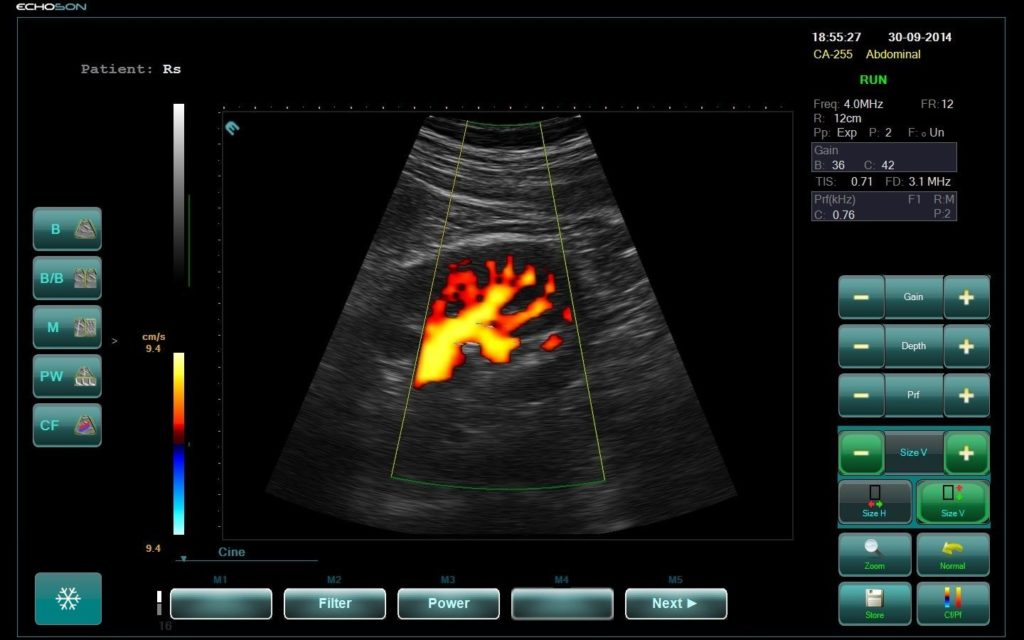

U.S.G., 2 D Echo with Colour Doppler

All types of ultrasound examinations-abdominal, Trans vaginal done. Colour Doppler studies for peripheral vasculature also done. 2 D Echocardiography can also perform on the same machine (siemens acuson X700). Doppler echocardiography is a procedure that uses ultrasound technology to examine the heart or blood vessels. An echocardiogram uses high frequency sound waves to create an image of the heart while the use of Doppler technology allows determination of the speed and direction of blood flow by utilizing the Doppler effect. An echocardiogram can, within certain limits, produce accurate assessment of the direction of blood flow and the velocity of blood and cardiac tissue at any arbitrary point using the Doppler effect.